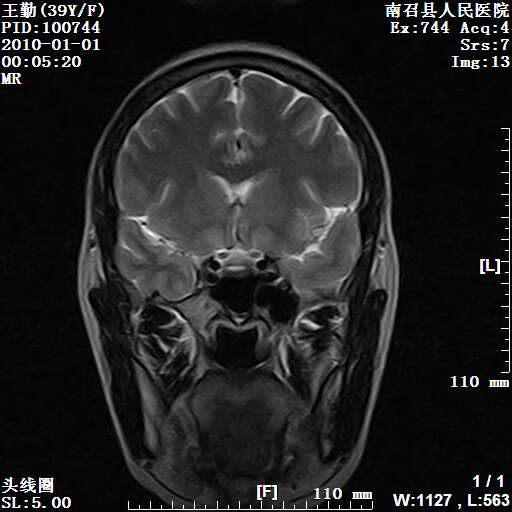

以下是引用随光逐影在2010-1-22 9:03:00的发言:[br]考虑左侧中颅窝(蝶骨翼区)脑膜瘤侵犯蝶骨翼并突入左侧眼眶。

以下是引用水过无痕在2010-1-22 14:55:00的发言:[br]一、定位:颅外占位;二、定性:恶性可能性大;三、组织来源:来源于左侧眼外直肌或其他部位;考虑为:横纹肌肉瘤>转移瘤>脑膜瘤.